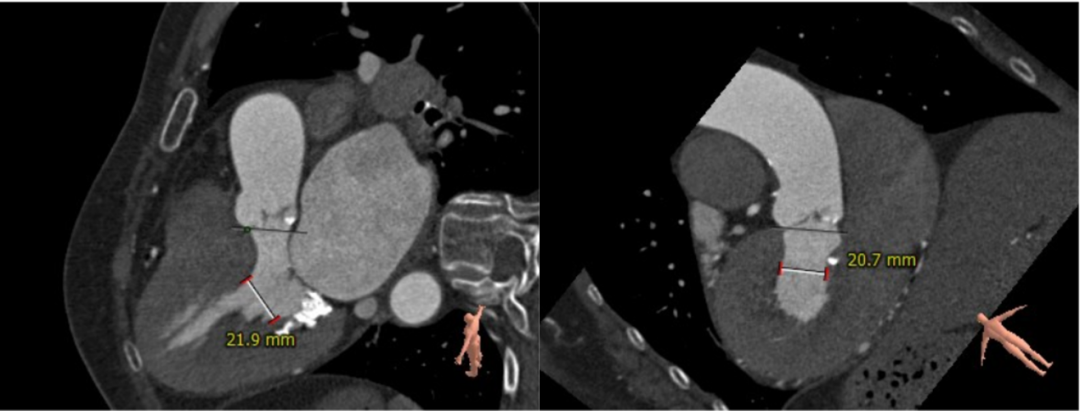

主动脉根部评估:

三叶式主动脉瓣 瓣环周长67.4mm

平均周长径21.5mm

STJ平面周长83.5mm

升主动脉最大直径34.6mm

左冠高度15.0mm 右冠高度14.7mm

SOV瓦式窦:平均周长径 32.0mm

LVOT最短径14.6mm